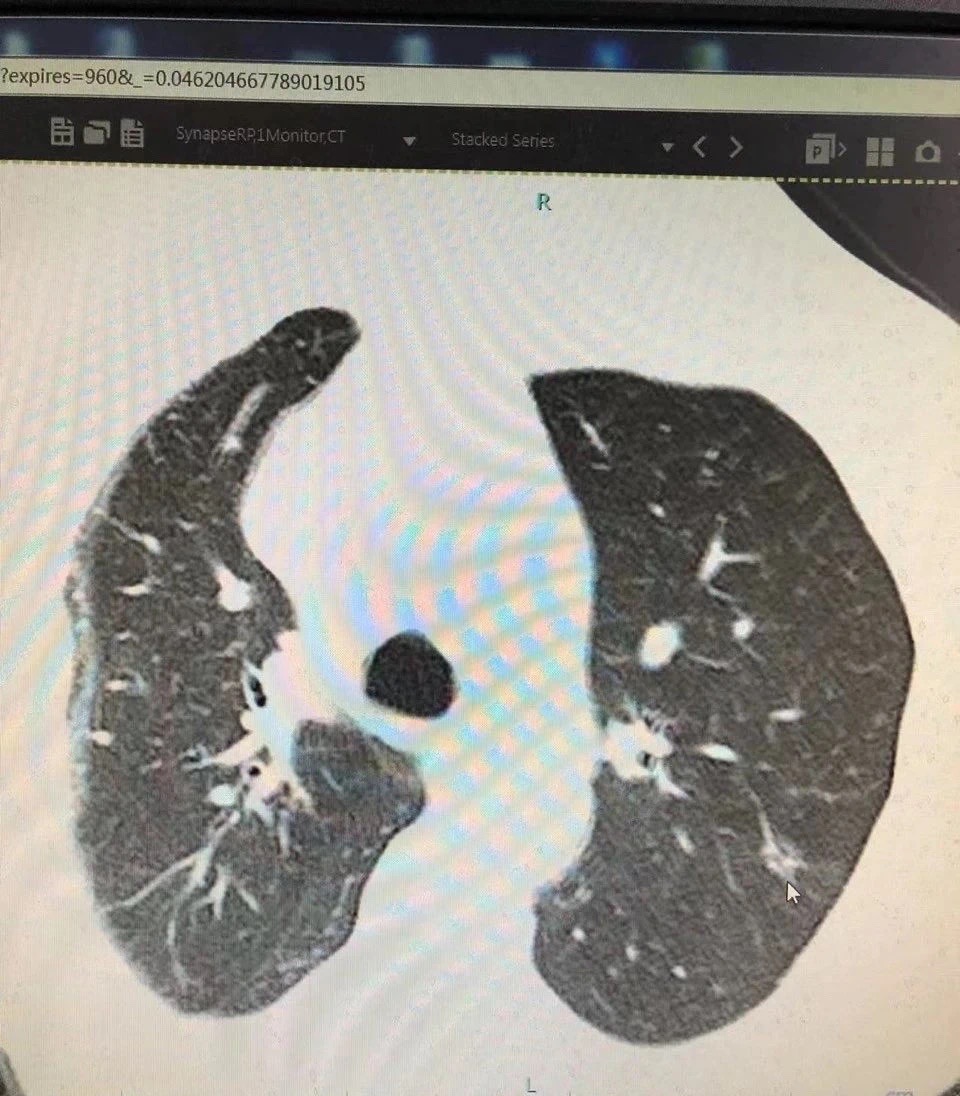

今年73岁的患者宋女士在两年前的体检中发现肺部磨玻璃结节。按照医嘱,宋女士定期在我院门诊复查。在今年3月的检查中发现,患者左上肺结节已扩大到5X8mm左右,且实性成分也比之前增加,形态也发生了变化,引起胸外科主任李政圣的注意。

李主任阅片后诊断患者左上肺结节有恶性肿瘤可能,建议住院手术治疗。但是又因肺部病灶小,难以定位,经过认真考虑,胸外科团队决定为患者施行肺小结节穿刺微弹簧圈定位术。